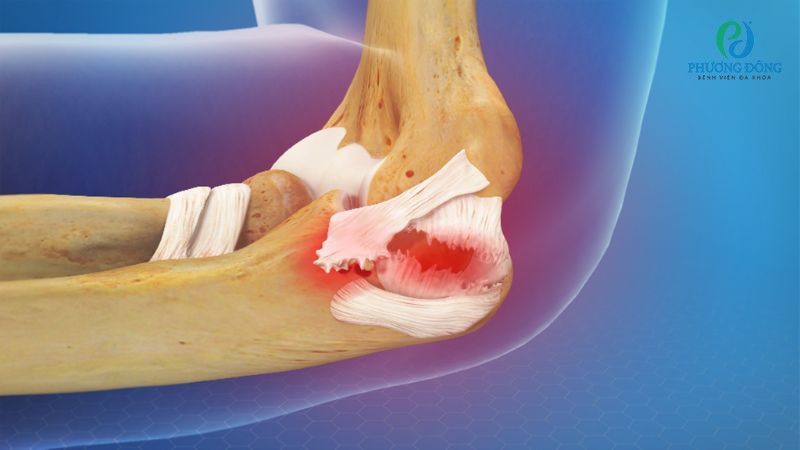

Tổn thương sụn khớp

Sụn khớp có cấu trúc trơn giãn, hỗ trợ việc cử động khớp diễn ra nhẹ nhàng, giảm lực va đập và phân bổ đều áp lực lên bề mặt khớp. Bộ phận này không có mạch máu, không chứa đầu mút thần kinh nên khi xảy ra chấn thương, sụn khớp không thể tự phục hồi.

Tổn thương sụn khớp không thể tự phục hồi

Tổn thương sụn khớp thường xuất hiện do các lực tác động đột ngột từ bên ngoài lên bề mặt khớp, gây bong hoặc vỡ sụn. Các mảnh sụn lớn khi này có thể tạo dị vật trong khớp, gây kẹt khớp.